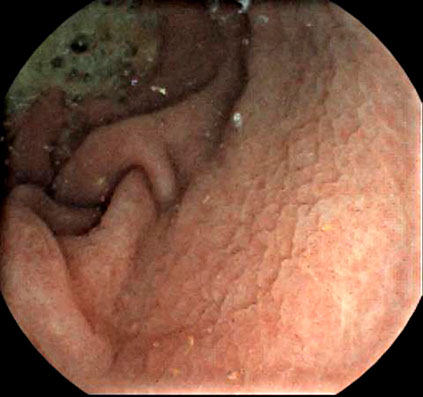

Case Gallery